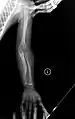

OI Type V in a child

Type V

Having the same clinical features as Type IV, it is distinguished histologically by "mesh-like" bone appearance. Further characterized by the "V triad" consisting of (a) radio-opaque band adjacent to growth plates, (b) hypertrophic calluses at fracture sites, and (c) calcification of the radio-ulnar interosseous membrane.[24]

OI Type V leads to calcification of the membrane between the two forearm bones, making it difficult to turn the wrist. Another symptom is abnormally large amounts of repair tissue (hyperplasic callus) at the site of fractures. Other features of this condition include radial head dislocation, long bone bowing, and mixed hearing loss.